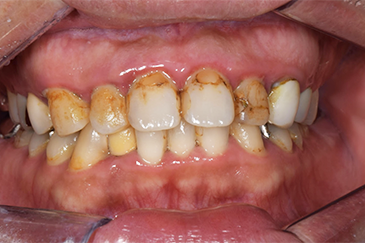

CASE 2

Before

After

基本情報

| 年齢・性別 | 30代・男性 |

|---|---|

| 主訴 | 歯石を取りたい |

| 治療内容 | 超音波スケーラーでの歯石除去 |

| 治療期間 | 60分 |

| 治療費 | 初診料を含め約4,500円 |

| リスク・副作用 | 歯ぐきに違和感や痛みを覚える場合がある。 1週間程度、歯を磨くといつもより出血することがある。 腫れていた歯ぐきが引き締まることで歯ぐきが下がった様に見える。 歯ぐきが下がることで歯がみしやすくなることがある。 一時的に歯の動揺(ゆれ)が増す場合がある。 |